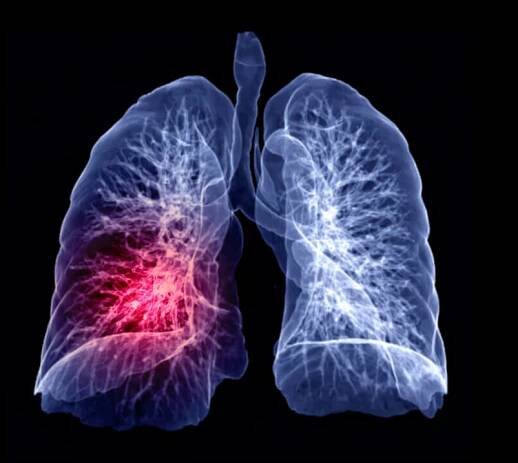

ObrázkyEmbolie plic

ct hrudník nebo plíce 3d vykreslování obraz na rozmazaném pozadí lidského těla pro diagnostiku tbc,tuberkulózy a covid-19 . - plicní embolie - stock snímky, obrázky a fotky